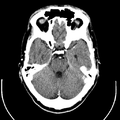

التصوير المَقْطَعي الحاسوبيX-ray computed tomography نظام تصوير بالأشعة السينية، يُسْتخدم لتصوير مختلف أجزاء الجسم مثل الرأس والقلب والبطن. ويستعين الأطباء بالتصوير المقطعي الحاسوبي على تشخيص الأمراض وعلاجها. وتسمى هذه التقنية أيضًا التصوير المقطعي المحوسب أو التصوير المقطعي المحوري المحوسب.

وللحصول على صورة أشعة مقطعية، يرقد المريض على طاولة تمر من خلال آلة فحص دائرية، تسمى المِسْند. وتوضع الطاولة بحيث يكون العضو المراد فحصه واقعًا عند منتصف المسند. وعن طريق أنبوب على المسند، تخرج أشعة سينية مخترقةً جسد المريض، ثم تدخل إلى مكشافات خاصة تقوم بتحليل الصورة التي ظهرت. ويدور المسند حول المريض للحصول على كثير من الصور من زوايا مختلفة. وبعد ذلك، يعالج الحاسوب المعلومات الآتية من المكشافات، لينتج صورة مقطعية مستعرضة على شاشة فيديو. وعن طريق تحريك الطاولة داخل المسْند، يمكن للأطباء الحصول على العديد من الفحوص للعضو نفسه، أو للجسد كله.

يمكن للأطباء أن ينظروا داخل جسم المريض عن طريق طلب إجراء مسح للعظام والأوعية الدموية والأدمغة والأنسجة الرخوة بفضل ماسح التصوير المقطعي الحاسوبي (CT). بعد إجراء أول فحص طبي بالأشعة المقطعية للمريض في عام 1971، استخدم أطباء الأشعة عمليات المسح لتشخيص الأورام والصدمات والتخطيط للعلاج الطبي والجراحي والإشعاعي في جميع أجزاء جسم الإنسان تقريباً.

داخل الجهاز على شكل كعكة الدونات، حيث يستلقي المرضى على الطاولة بينما يتحرك ببطء عبر الماسح الضوئي، تدور الآلة حولها. أثناء دورانه، يرسل شعاعاً رفيعاً من الأشعة السينية عبر الجسم، والذي يتم جمعه على الجانب الآخر من الجهاز ونقله إلى برنامج حاسوب، حيث يتم تحميله على شاشة لعرضها على تقنيي التصوير المقطعي المحوسب.